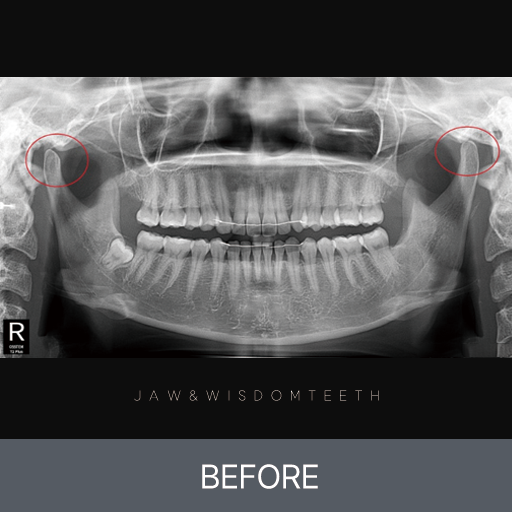

사랑니 CASE